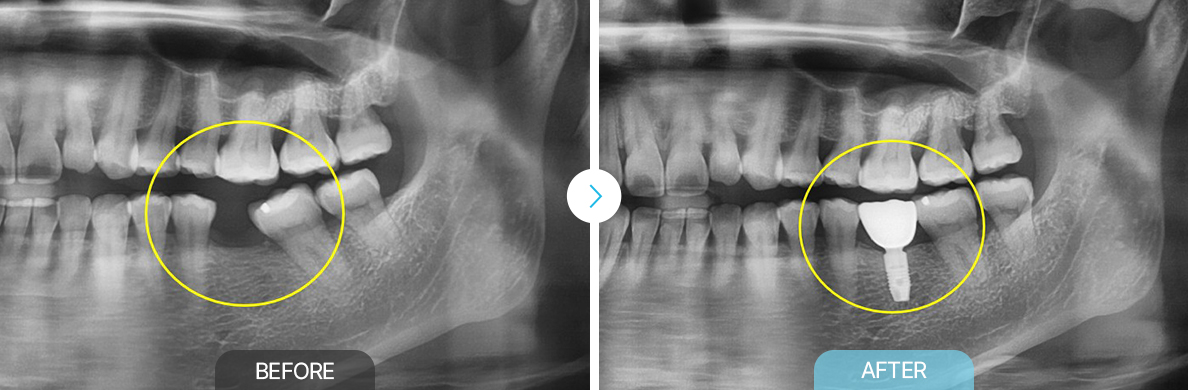

BEFOREAFTERBEFOREAFTER